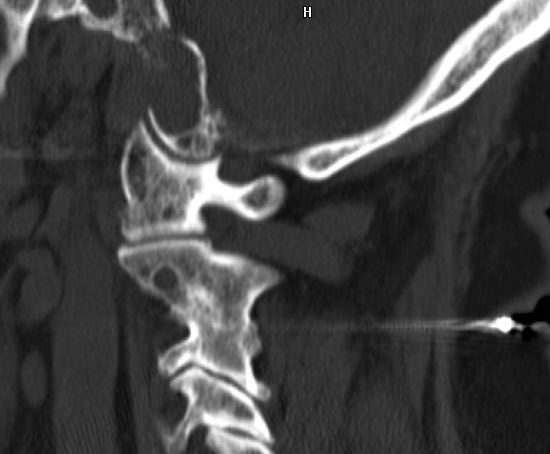

| 79-jährige Frau mit metastasiertem Nierenzellkarzinom. Destruktion der Schädelbasis links. | ||||